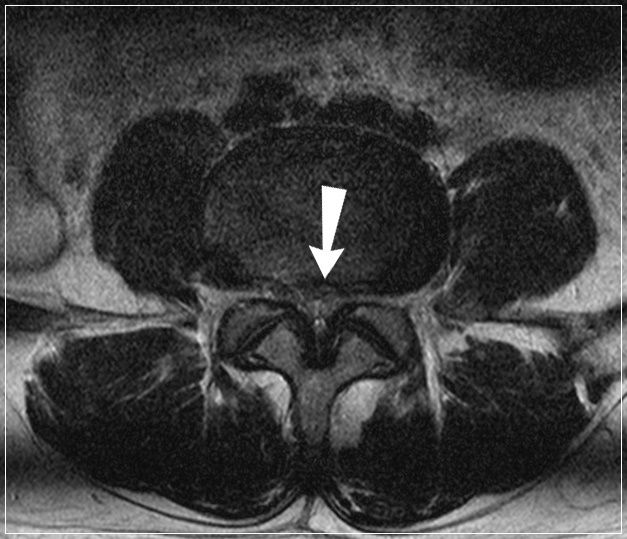

건강보험심사평가원 통계에 따르면, 2017년 척추관협착증 환자 수는 154여만 명에 달합니다. 척추관협착증은 척추 뼈 사이 추간공이 퇴행성 변화 혹은 다른 질환으로 인해 좁아지면서 척추 신경을 눌러 생기는 질환입니다 중년 이후에 많이 나타나는 흔한 질환의 하나로 말 그대로 신경이 지나가는 공간인 척추관이 좁아져서 신경을 누르는 병입니다.

척추관 협착증에서는 주로 뼈, 관절과 같은 딱딱한 조직이 신경을 누릅니다. 통증의 양상을 보면, 허리 디스크는 빠른 시간 내에 진행하는 경우가 많고 척추관 협착증은 오랜 시간에 걸쳐 서서히 나타나는 경우가 많습니다. 또한 척추관 협착증의 특징적인 증상으로 간헐적 파행이 있습니다. 이는 허리 디스크의 증상과 구별되는 것으로 앉아 있을 때는 괜찮은데 조금만 걸어도 다리가 저리고 아파서 앉아 쉬었다가 다시 걸어야 하는 보행 장애 증상을 말합니다.